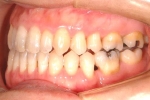

カテゴリー:開咬(overbiteがマイナスのもの)

| 初診時